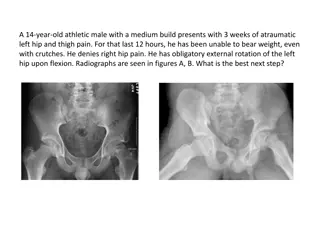

Slipped Capital Femoral Epiphysis: Adolescent Hip Disorder